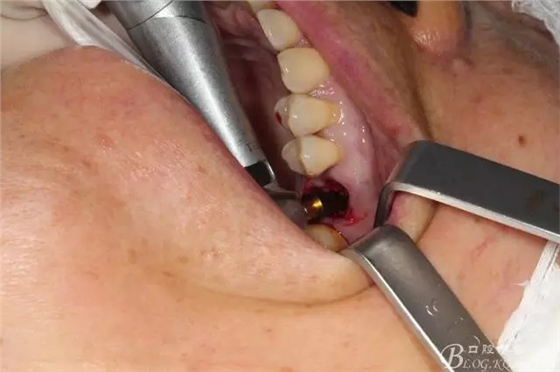

拔牙 當(dāng)然這種手術(shù)我必須不翻瓣零翻瓣

簡(jiǎn)單備洞以后植入種植體 植體和頰側(cè)空間距離大于2毫米 注意沒有植骨

這個(gè)角度更能看到植體與頰側(cè)骨壁的空間了